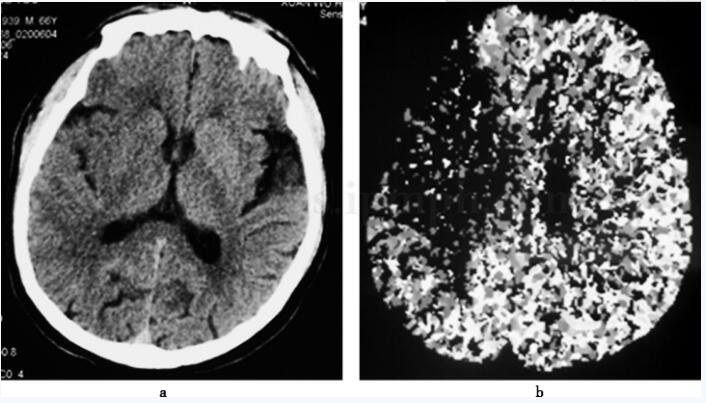

入院时诊断为脑梗死(右侧大脑中动脉主干闭塞),心律失常(心房纤颤)。入院当天CT扫描提示右侧大脑半球、基底核密度稍减低,右侧颞叶脑沟变浅,右大脑中动脉供血区灌注降低(图1)。予以静脉输注前列腺素E10μg,每日1次;田七人参注射液350mg,每日1次;20%甘露醇125ml,每6小时1次;甘油果糖250ml,每12小时1次;口服阿司匹林肠溶片100mg,每日1次;福辛普利5mg,每日1次;美托洛尔12.5mg,每日1次;尼卡地平40mg,每日2次;胺碘酮100mg,每日2次。经上述治疗病情基本平稳。入院第4天复查头颅CT扫描,提示右侧大脑中动脉供血区域大面积脑梗死(图2)。入院第7天晨起突感胸闷,持续30分钟,但不伴胸疼,舌下含服硝酸甘油后有所缓解。进一步检查发现双肺呼吸音粗,肺底可闻及少许湿啰音;心率62次/分,律不齐,未闻及杂音;双下肢无水肿。此时心肌酶检测在正常范围(表1)。心脏Doppler超声显示左心扩大,左室节段性运动不良,左室壁肥厚。心内科会诊后不排除冠心病可能,增加口服单硝酸异山梨酯缓释胶囊50mg,每日1次;劳拉西泮0.5mg,每晚1次;胸闷有所好转。当日下午2时再次胸闷不适,同时右腿麻木、疼痛,双下肢膑骨下10cm处周经(右侧31.6厘米,左侧31.2厘米)基本对称。舌下含化硝酸甘油0.5mg后胸闷稍有缓解。入院第9天下午2时右侧髋关节疼痛,但测量双下肢周径较前无明显变化,经口服布洛芬缓释胶囊0.3g、加强活动和热敷后疼痛缓解。入院第11天双下肢轻度凹陷性水肿。入院第12天上午9时胸闷憋气加重,舌下含化硝酸甘油(0.5mg)不能缓解。复查心肌酶仍在正常范围内;心电图显示窦性心动过速(132次/分),右束支传导阻滞,V1~V4导联ST段压低明显,T波倒置。考虑心功能不全,予以呋塞米40mg,每日静脉注射1次;硝酸甘油5mg加入生理盐水49ml,每小时6ml泵入;地高辛0.125mg,每日口服1次;抬高床头30度;症状略有好转。当日下午5时胸闷、憋气明显,血气分析(表2)提示低氧血症(PaO247﹒6mmHg)、低碳酸血症(PaCO231﹒0mmHg)、轻度碱中毒(pH7.513)。再次复查心肌酶仍在正常范围,但D‐二聚体(正常值<0.4mg/L)连续3次增高(5.5mg/L,2.6mg/L,1.4mg/L)。床旁X线胸片(图3)显示心影增大。根据上述临床表现过程拟诊断为肺血栓栓塞,立即开始抗凝治疗。予以口服华法林,每日3mg;皮下注射低分子肝素4000IU,每12小时1次;同时监测凝血指标(表3),并调整药物用量。入院第14天左胸前区阵发性钝痛,伴胸闷、憋气。查体心音有力,心律不齐,未闻及杂音;两肺可闻及湿啰音。因病情加重转入神经内科重症监护病房(N‐ICU)。转入当天胸部螺旋CT扫描提示双侧肺动脉中心型血栓栓塞(图4)。下肢血管超声检查提示右下肢腘静脉前壁附壁血栓形成,左侧胫前静脉和胫后静脉远端、双腓静脉血栓形成,双下肢静脉红细胞聚集征,左侧下肢静脉瓣功能轻度不全(图5)。国际标准化比率(INR)2.67,活化部分凝血酶时间(APTT)69s。继续抗凝治疗,并抬高双下肢,改善血液回流。此后病情逐渐趋于稳定,未再诉胸闷、胸痛、气短不适,双肺呼吸音清晰,双下肢水肿消退,N‐ICU治疗22天后病情平稳转回普通病区。入院50天病情好转出院。继续口服华法林3mg,每日1次,连续11个月。

图1头颅CT(2006‐4‐23)

右侧大脑半球、基底核密度稍减低,右侧颞叶脑沟变浅(a)。灌注脑血容量图:右侧大脑中动脉供血区脑血流量较对侧明显减少(b)